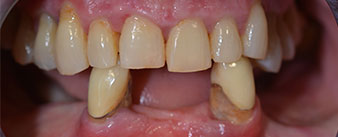

The 64-year-old patient presented with residual dentition of teeth 38, 33 and 43 and a clasp denture in the mandible (Fig. 1 and 2).

The necessary periodontal treatment and extraction in the maxilla was to be performed at a later point in time, as the patient is a teacher and was busy with school leaving exams at the time. She could neither eat nor speak properly, as the temporary prosthesis was very fragile, breaking regularly and under the slightest strain.

Following an explanation of the various treatment options open to her, the patient decided on extraction of the residual dentition in the mandible, an immediate implantation and treatment with the Fast & Fixed method (bredent medical), whereby the provisional fixed denture is screwed onto four implants on the same day as the surgery. The goal was to operate on the patient on the Friday so that she could assist in the oral examinations on the following Monday.